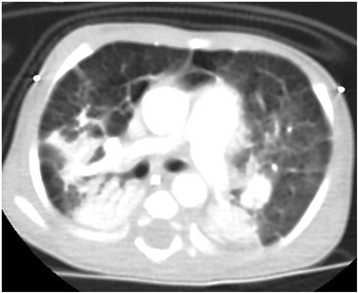

Case presentation: Here, we describe a 1-year-old Saudi female child with respiratory distress at birth. The child then had recurrent lower respiratory tract infections, bilateral lung emphysema with basal atelectasis, bronchospasm, pulmonary artery hypertension, and oxygen and mechanical ventilation dependency. Molecular testing showed a new pathogenic variant of one copy of c.3153dupC in exon 21 in the FLNA gene.